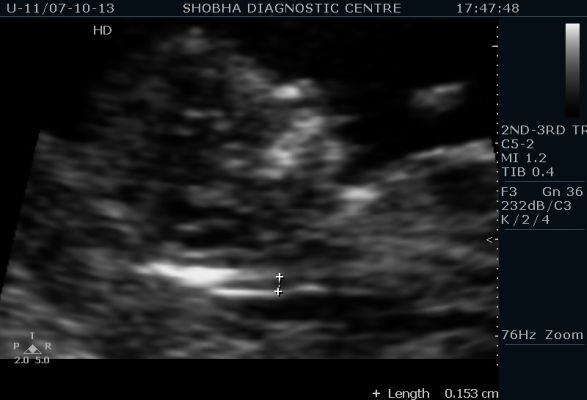

ULTRASOUND TEST: This is done at 11-13+6 weeks and is performed by FMF (Fetal Medicine Foundation) certified operator. All the three radiologists at shobha diagnostic centre are FMF certified. This involves evaluation of Nuchal Translucency (fluid behind baby’s neck) and other markers for chromosomal abnormality like nasal bone. These measurements are abnormal in Down’s syndrome. The overall fetal anatomy is also checked at this time.